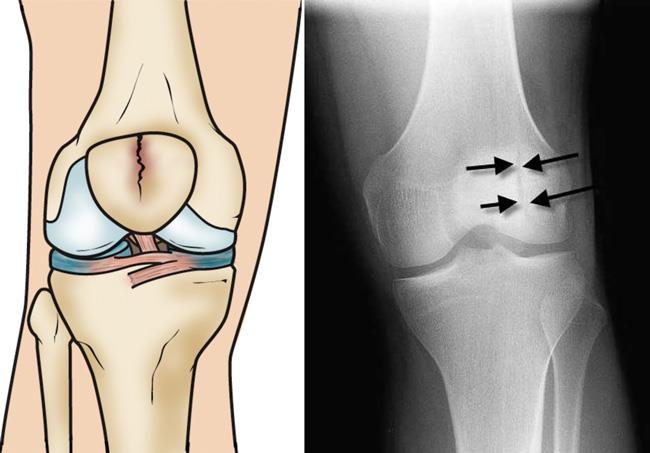

• 3 новых хирургических метода лечения переломов надколенника

3 новых хирургических метода лечения переломов надколенника

Переломы надколенника составляют 1% всех случаев травм, и в настоящее время рекомендуемой хирургической процедурой для лечения простых поперечных переломов надколенника со смещением суставной поверхности является проволока с натяжением (TBW), которая действует как антинатяжное устройство, когда надколенник (растягивающий